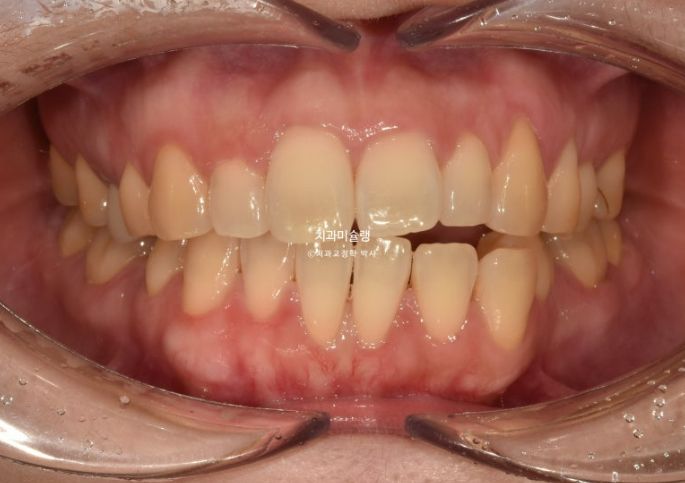

24.06

아래 앞니 두 개 잇몸이 유독 내려가 있습니다.

정중선 기준 한쪽만 개방교합이 있는데 한쪽방향으로 혀내밀기 습관때문에 생긴 개방교합일 수 있고 유지장치 변형에 의해 치열이 일그러진 것 일수도 있습니다.

소구치에 윗니와 아랫니가 엇갈려 물리는 가위교합도 보입니다.

큰어금니 교합도 좋은 편 입니다.